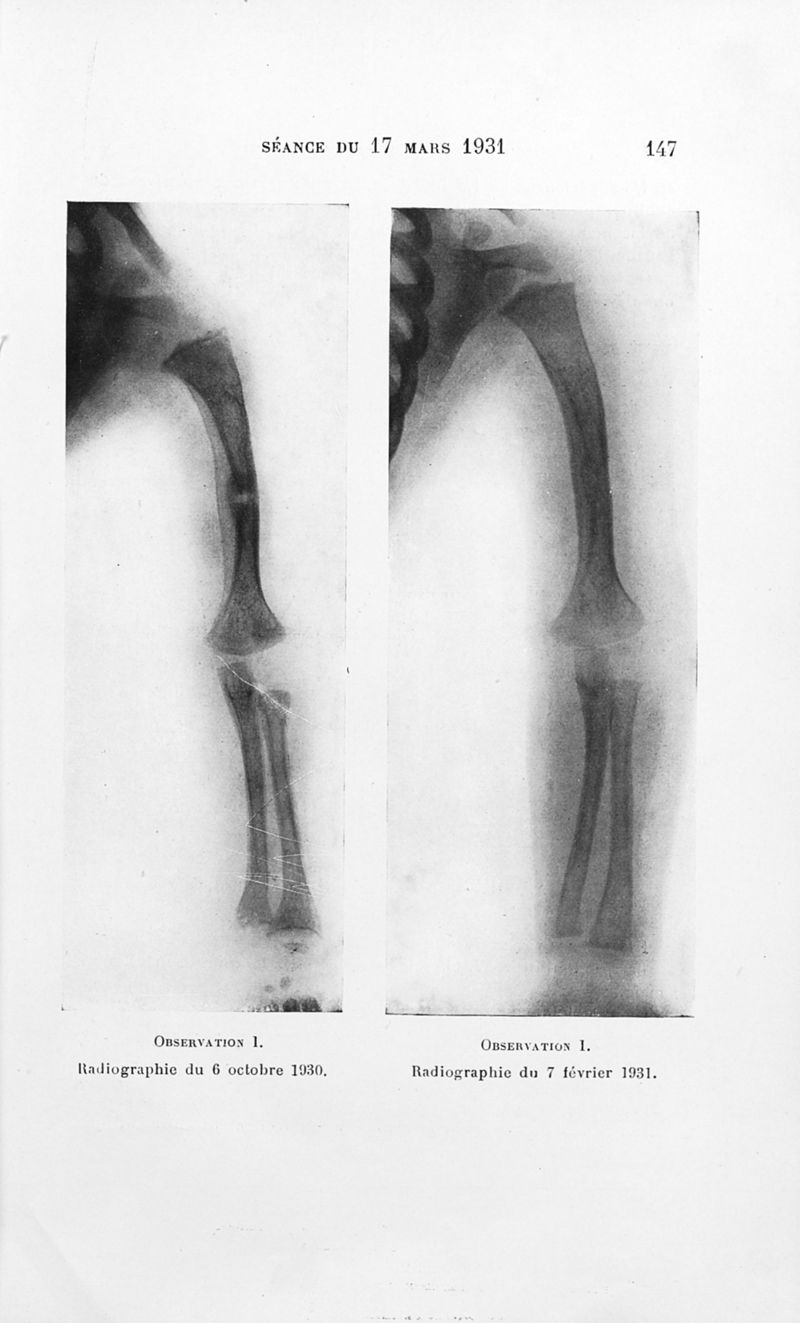

Bulletins de la société de pédiatrie de Paris

Tome vingt-neuvième. - Paris : Masson et Cie, 1931.